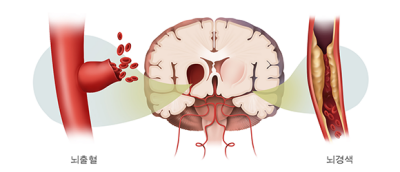

우리나라에서 단일 질환으로 사망률 1위는 뇌졸중이라고 하는데요. 뇌졸중은 뇌의 혈관이 좁아지면서 혈관이 막히며 발생하는 질환입니다.

두통은 뇌경색보다 뇌출혈에서 더 많이 나타나고 평상시에 일반적인 두통이 아니라 강도가 훨씬 셉니다.